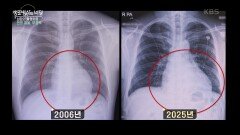

재생09:14생로병사의 비밀고령 환자의 희망 - 표적치료제 | KBS 260422 방송